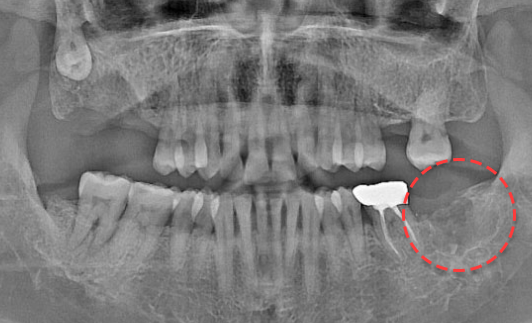

• BEFORE

오른쪽 하악 매복 사랑니 발치 Before X-Ray

치료시작일

2020.04.24

AFTER

오른쪽 하악 매복 사랑니 발치 After X-Ray

치료종료일

2020.06.24

오른쪽 하악 매복 사랑니 발치